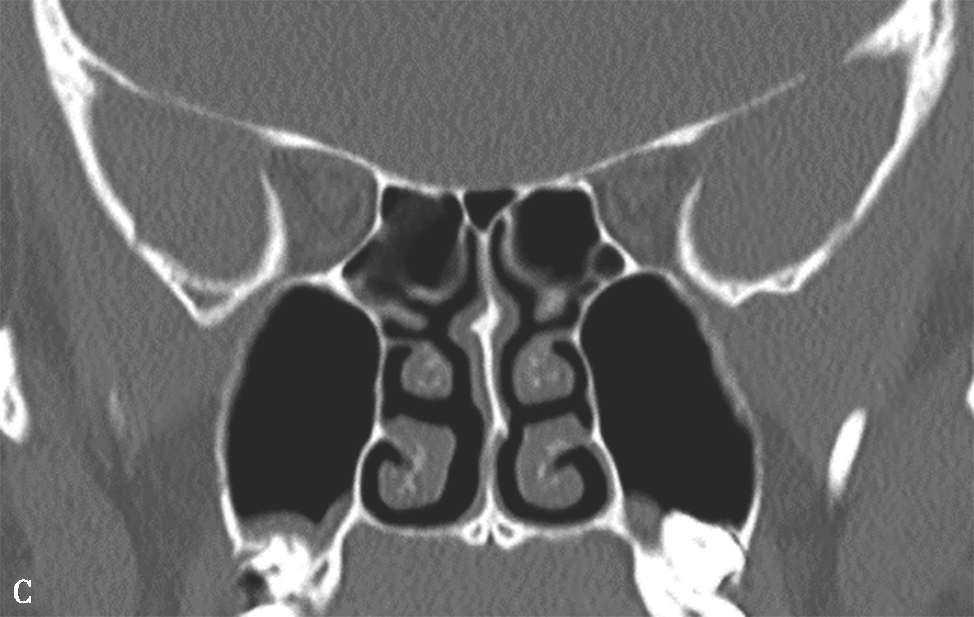

5.筛泡(bulla ethmoidalis)

即中组筛房,位于鼻丘后,由1~3个气房构成,内下壁与筛骨钩突间形成半月裂间隙。筛泡过度气化,可能造成筛漏斗及半月裂狭窄,影响引流;过度气化至眶下壁时,称为眶下气房,又称Haller气房,也可能影响上颌窦的引流(图1-3-6)。

图1-3-6 筛泡解剖变异

A.双侧Haller气房;B.左侧筛大泡